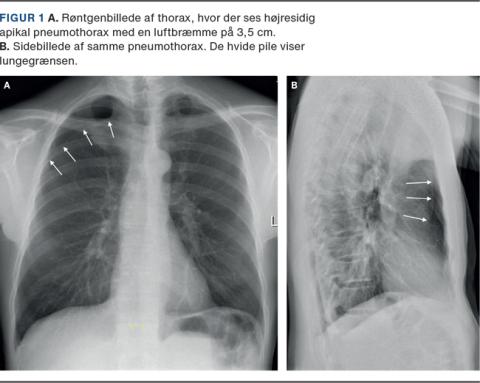

En lungerask patient med kroniske nakke-ryg-smerter søgte en alment praktiserende læge pga. en subjektiv fornemmelse af »tung vejrtrækning«. Han blev henvist til røntgenoptagelse af thorax, hvor man fandt højresidig pneumothorax (Figur 1).